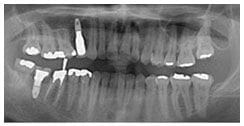

X 光片

術前X光片